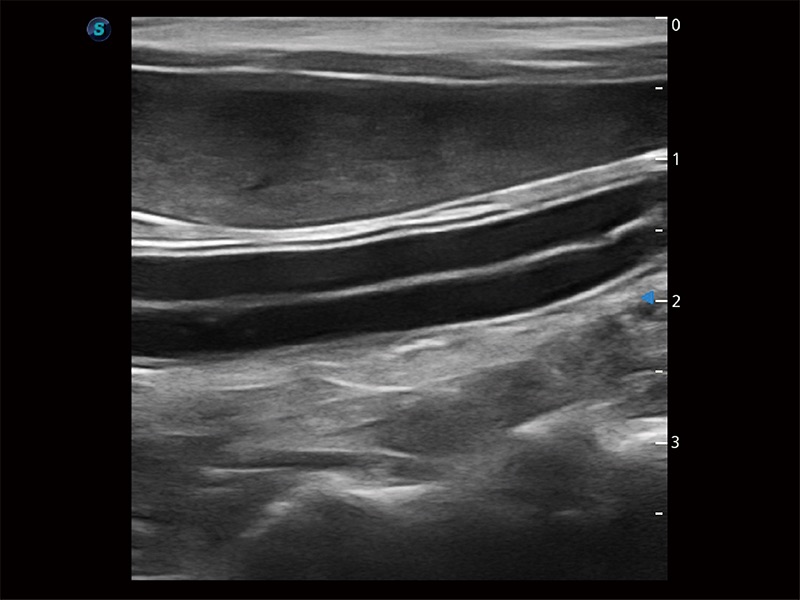

極大提升超低速微細血流的檢出能力,同時更精準地濾除軟組織和超聲信號,為獸用醫(yī)生提供以往無法通過常規(guī)血流獲得的疾病診斷信息。